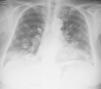

We report the case of a 76-year-old patient, with no toxic habits, hypertensive, with the chance finding on a chest X-ray of a “balloon release” image, finally diagnosed as LG. The patient was asymptomatic. No significant findings were observed on physical examination and lung auscultation was normal. Minimal leukocytosis was seen on clinical laboratory testing, which was normal for tumor markers. Imaging tests showed the presence of bilateral pulmonary nodules, predominantly in the lower lobes (Fig. 1), some with air bronchogram sign and occasional central cavities. Transbronchial and transthoracic biopsies were performed, but did not yield a diagnosis. An atypical surgical resection of a pulmonary node was performed, showing polymorphous lymphocytic infiltrate with an angiocentric and angiodestructive pattern, consisting of aberrant CD20 positive lymphoid cells on a background of small sized lymphocytes. An EBER probe was used to demonstrate the presence of EBV-infected cells, establishing a definitive diagnosis of grade 2 LG.2

Imaging tests typically show bilateral nodules and masses with peribronchovascular distribution, mainly in the lower lobes, which may converge or form central cavities. FDG uptake on PET is variable.4